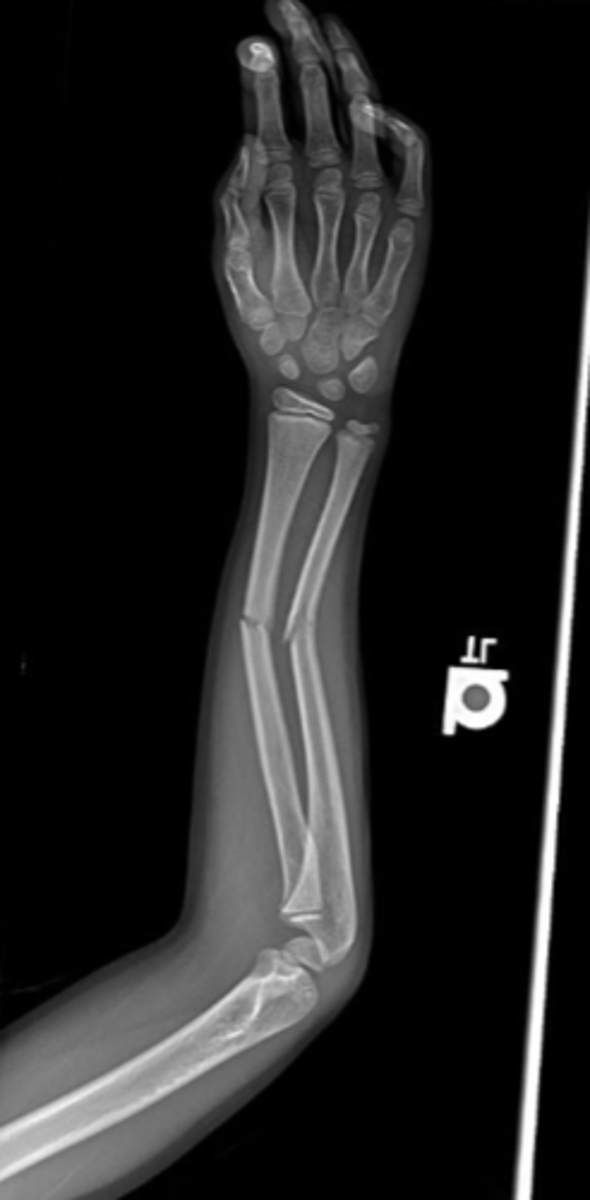

How do we get best imaging of a fracture

Xray assessment

What is an open/compound fracture

- skin break

- fracture is piercing skin, exposing bone

What are the types of unstable fractures

- oblique

- spiral

- comminuted (fragmented/cracked & compressed bone)